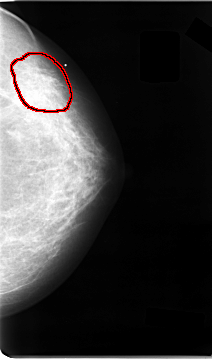

FILE: C_0026_1.LEFT_CC.OVERLAY

TOTAL_ABNORMALITIES 1

ABNORMALITY 1

LESION_TYPE CALCIFICATION TYPE AMORPHOUS DISTRIBUTION CLUSTERED

LESION_TYPE MASS SHAPE ARCHITECTURAL_DISTORTION MARGINS ILL_DEFINED

ASSESSMENT 4

SUBTLETY 2

PATHOLOGY MALIGNANT

TOTAL_OUTLINES 1

BOUNDARY

LEFT_CC LINES 4672 PIXELS_PER_LINE 2744 BITS_PER_PIXEL 12 RESOLUTION 50 OVERLAY